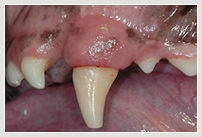

Zahnfraktur Katze Zahnfraktur Katze vorn Vergleich Katze nach Wurzelbehandlung u. Plombe

Zahnfraktur Hund Zahnfraktur Hund in Behandlung Zahnfraktur Hund mit Plombe